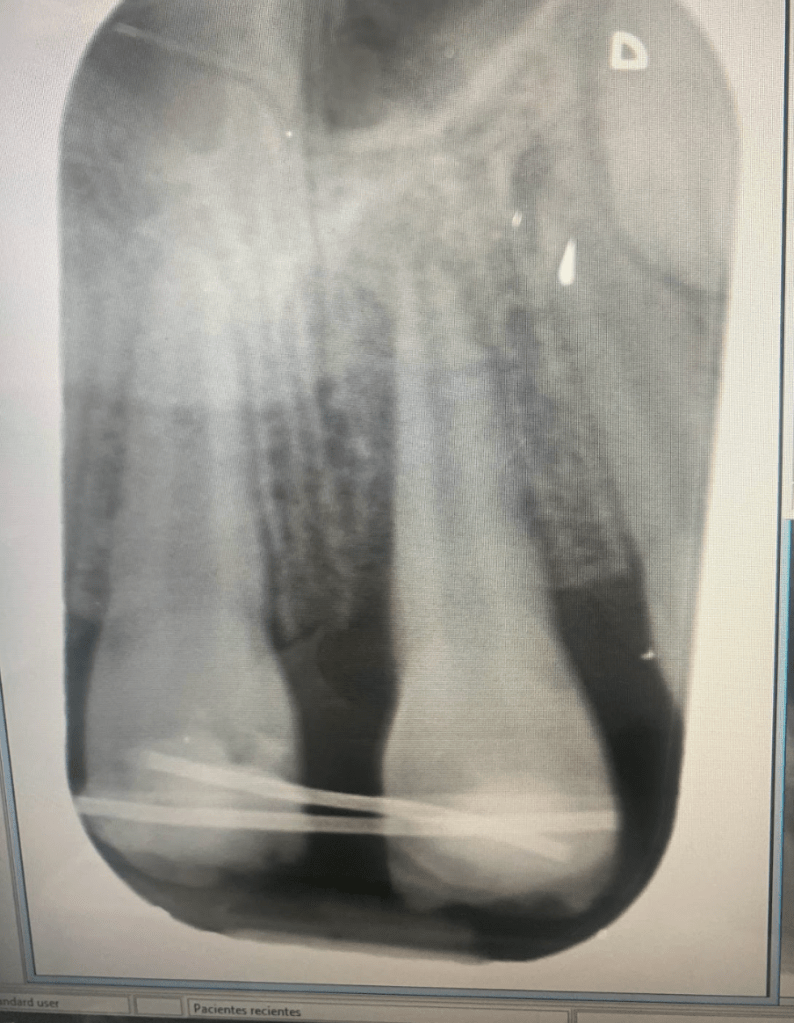

Fractura con exposición pulgar

Reconstrucción con recubrimiento pulgar indirecto